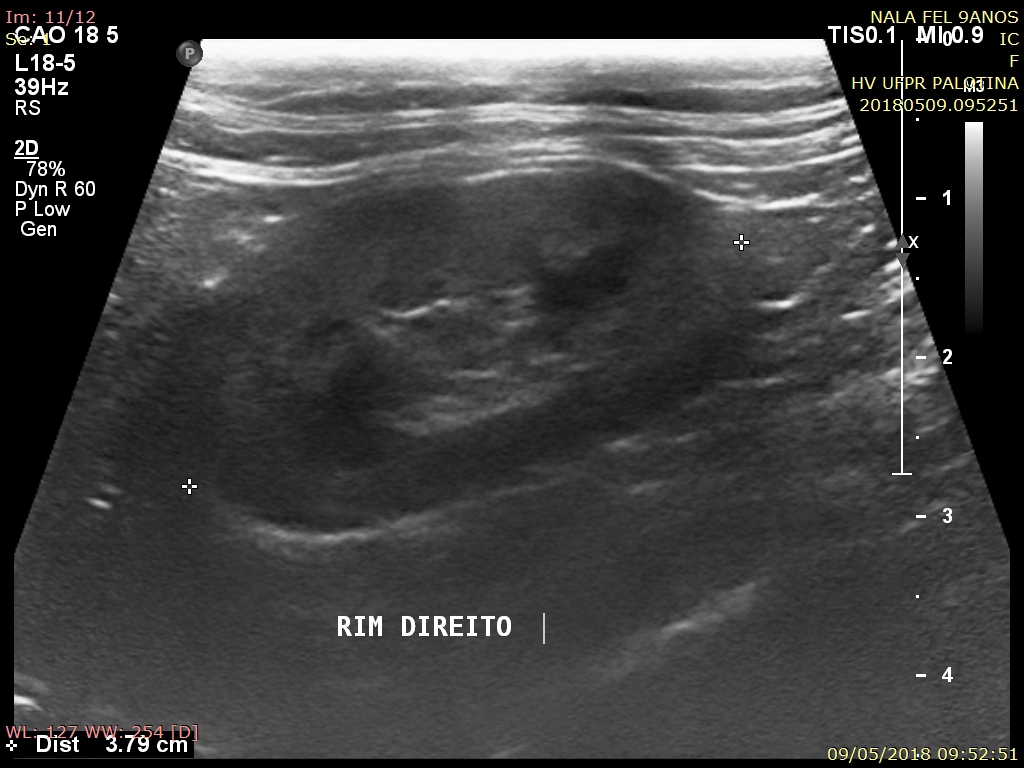

O exame ultrassonográfico é uma ferramenta diagnóstica imprescindível na avaliação da integridade renal, já que fornece informações importantes a respeito da arquitetura e das dimensões renais. Os rins são facilmente visualizados na ultrassonografia, a qual permite avaliar o parênquima do órgão, diagnosticar possíveis afecções, e monitorar o grau de comprometimento tecidual. Os gatos apresentam predisposição ao desenvolvimento de nefropatias, especialmente os mais idosos, por isso o uso do ultrassom demonstra alto grau de importância no diagnóstico precoce. O presente trabalho avaliou 12 gatos provenientes da rotina do Hospital Veterinário da Universidade Federal do Paraná, Setor Palotina, nos quais o tamanho renal demonstrou média e desvio padrão de 3,52 ± 0,45cm para o rim esquerdo e 3,64 ± 0,34cm para rim direito, a ecogenicidade de cortical se mostrou aumentada em sua maioria, sendo um achado normal devido ao acúmulo de gordura tubular. Os parâmetros de topografia, forma, contorno e características de pelve renal se mostraram dentro da faixa de normalidade, sendo as alterações em relação e diferenciação corticomedular, e ecogenicidade de cortical as de maior importância.